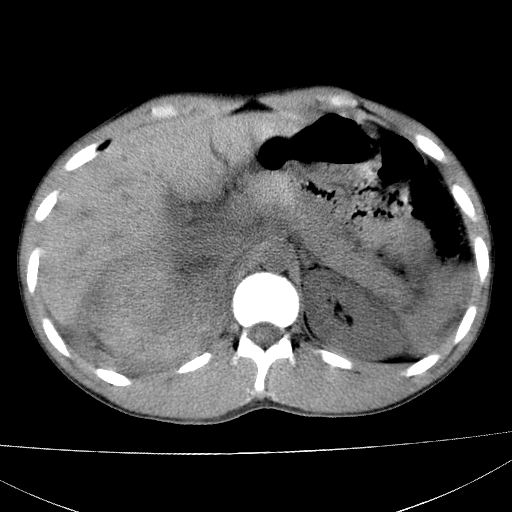

标题: CT15860:男,21岁,腹部外伤2小时伴胸疼。 [打印本页]

标题: CT15860:男,21岁,腹部外伤2小时伴胸疼。

肝脏及肾脏明显有损伤性改变并激发腹腔内积液(血),以肝脏撕裂及肾周积血显著。

1)肝破裂伴腹腔积液(血)。2)右肾破裂伴右肾包膜下及肾周血肿。3)腹部空腔脏器穿孔可能。4)右侧少量胸腔积液(血)。

肝肾挫裂伤,右肾周及包膜下血肿,腹腔积液,不排除空腔脏器穿孔,建议行增强检查

肝、右肾包膜下血肿,右侧腰大肌及腹膜后血肿;腹腔少量积血;腹腔疑有少量游离气体伴肠破裂。

肝右肾挫裂伤,右肾包膜下及肾周血肿.胸腹腔少量积液.脾脏下部密度稍不均,必要时,增强.

1肝挫伤伴腹腔积液。2右肾挫裂伤伴右肾包膜及肾后间隙肿血肿。3右肾脏周围的积气,十二指肠显示结构不清,考虑十二指肠降部破裂可能性大。